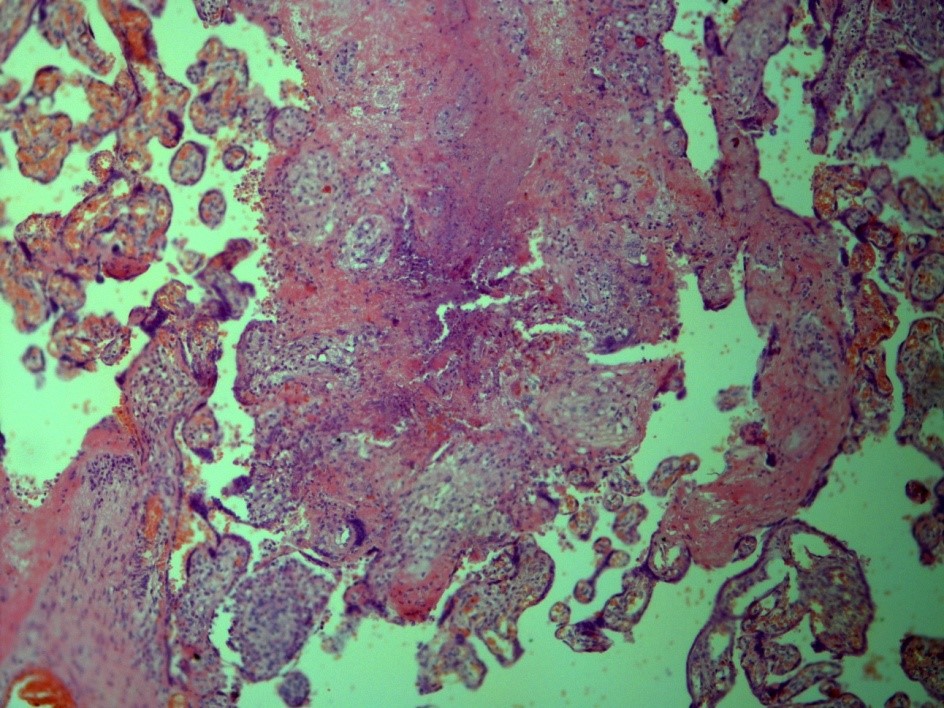

Our own case demonstrates an extremely rare case of TB of placenta in young woman, suffering from genital TB, which was overlooked before delivery. This woman had not known contact with TB infection, had no history of TB, had no complaints before pregnancy and had no special complaints in time of the pregnancy, excluding common ones for this condition. The delivery was in-time with a healthy full-term baby. In the Russian Federation the investigation of the placenta is a standard procedure, and it revealed TB inflammation (Figure 1) and Mtb in the placenta (Figure 2).